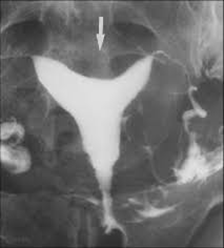

Indentation in superior pole of uterus

Arcuate uterus